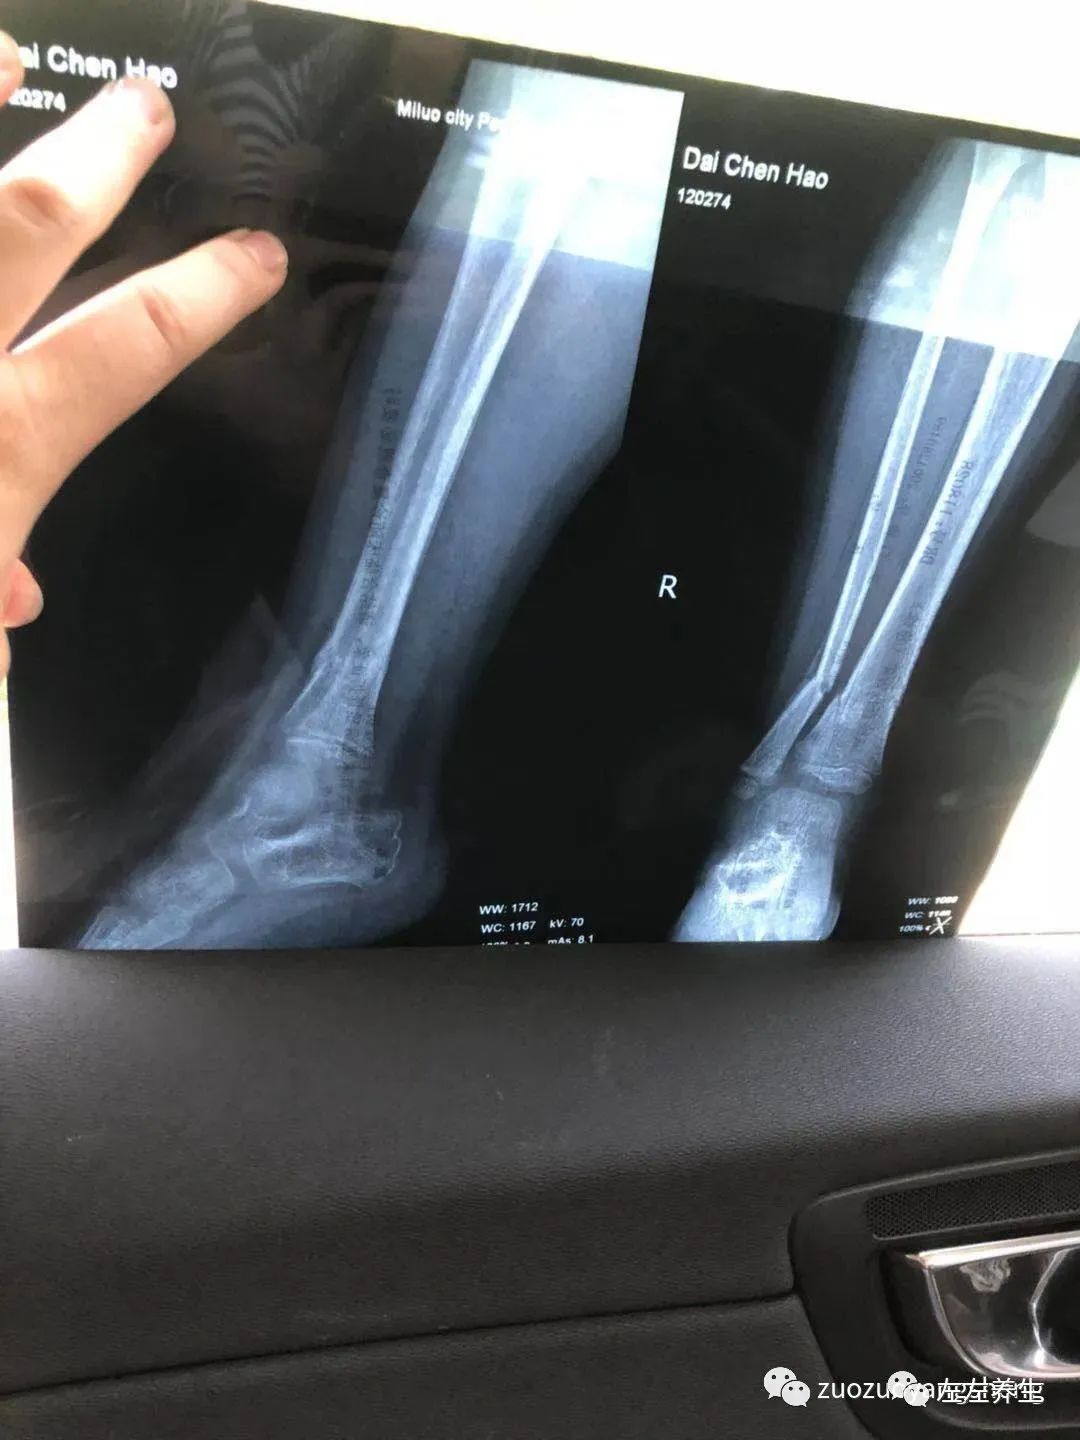

附检测单据:

孩子因为拆了石膏,安全感全失,吵闹了两天腿疼。同学说这个是正常现象,看了拍照发给他的片子后说,骨裂还是这么多要注意一下就好。